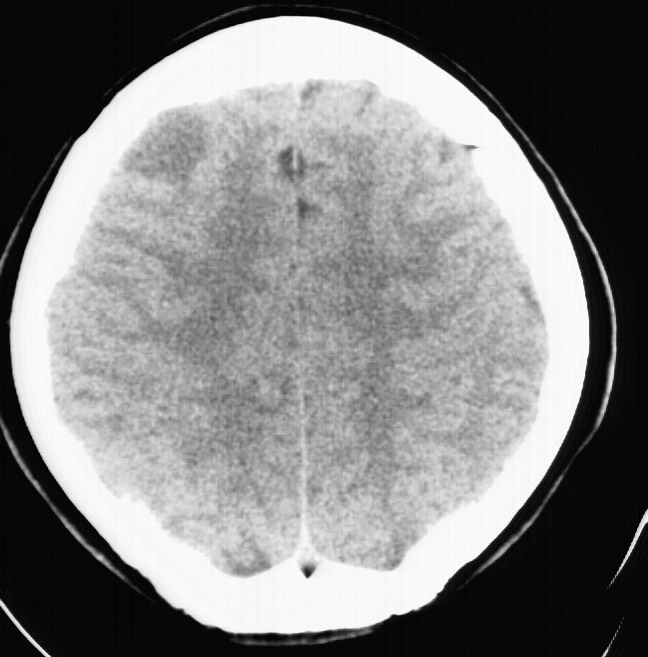

标题: CT5853:右额叶上部占位请会诊

女,34岁,自述头晕胀2年,近期感精神恍惚,无发热,实验室检查阴性。

水肿及强化都不明显!也没见钙化影!考虑i级星型细胞瘤可能性大!

右顶叶靠近脑表面圆形低密度灶,周围无水肿及占位效应,增强病灶无明显强化,考虑:右顶叶低分级星型细胞瘤。

右额叶上部皮质区见类圆形低密度区,边界不清,无强化,无钙化。

支持大多数战友的意见,1级星形细胞瘤。